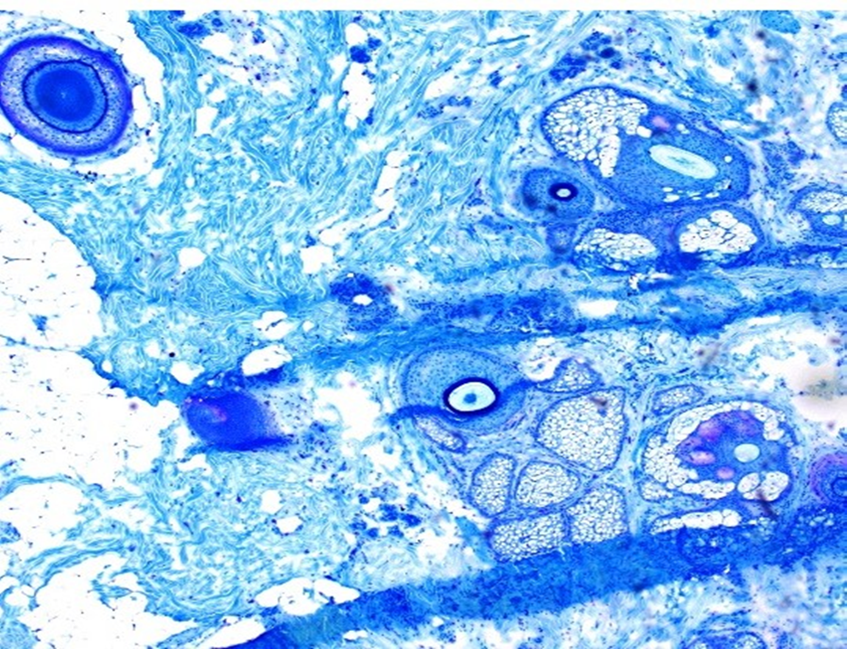

Martius Scarlet Blue

This is an example of a slide stained by Martius Scarlet Blue to demonstrate Fibrin.

All the fibrin should be brightly coloured and distinguishable from other structures.There should be good colour separation between the dyes for red blood cells (yellow), muscle (red) and collagen (blue). The nuclear staining should be dark blue or black

This is an excellent example that scored 10/10.